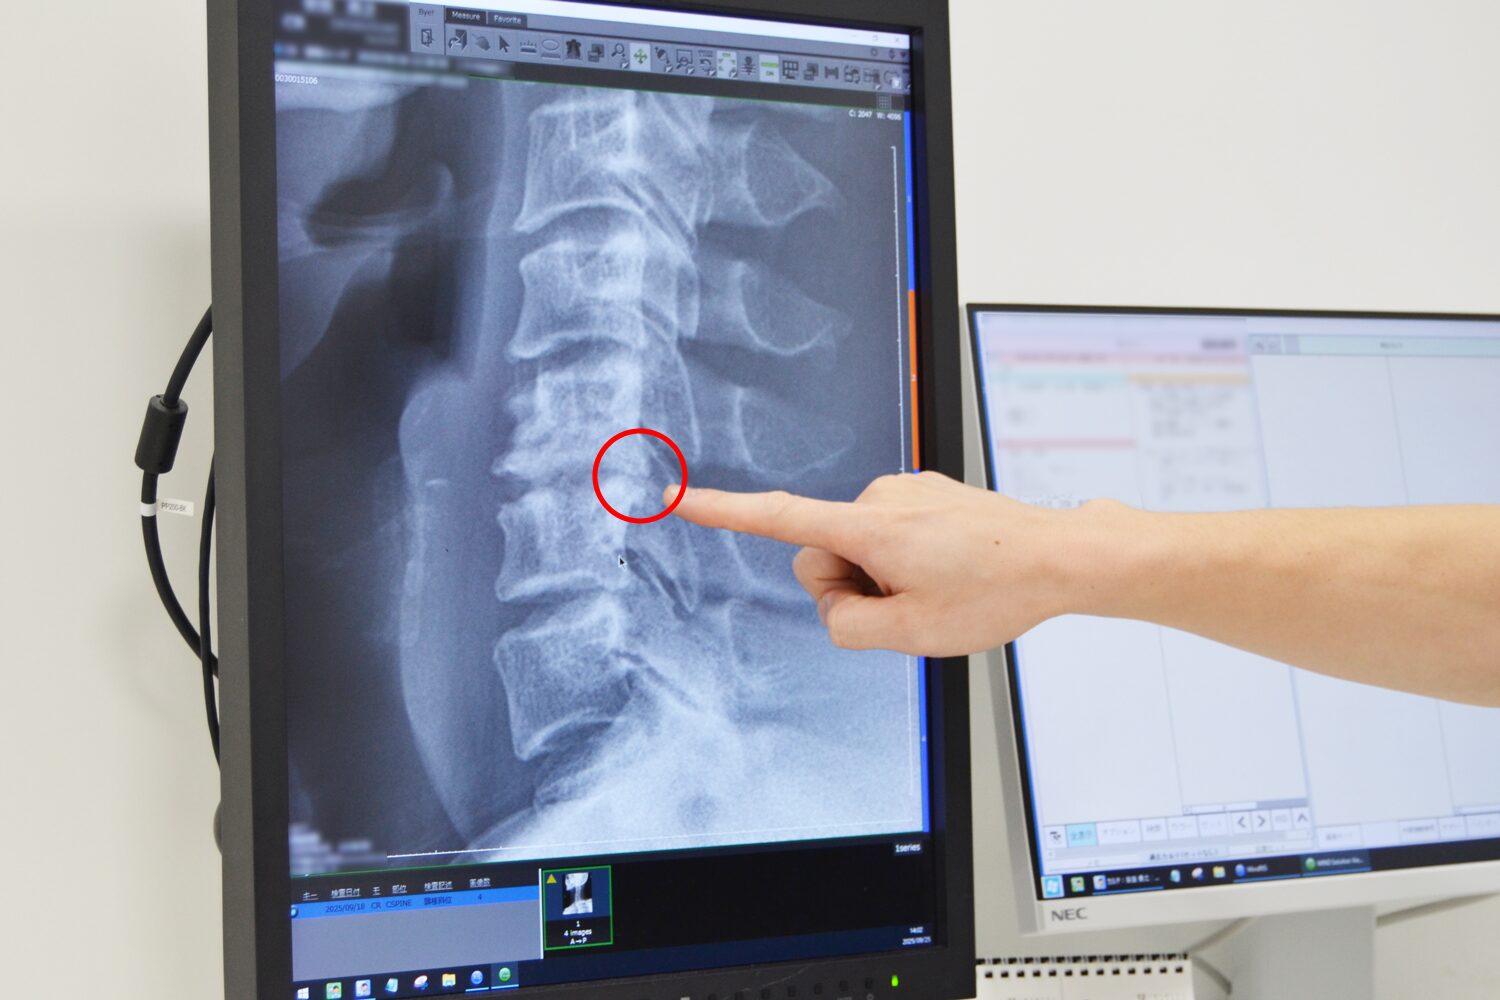

頚椎症のレントゲン画像

こちらが頚椎症の実際のレントゲン画像なのですが、骨の形状が変化して出っぱっているのが確認できます。このように骨がぴょこんと出てくると、首の骨の後ろに通っている神経に骨が触ってしまって腕や手がびりびりしてしまうことがあります。

こちらは斜めから見ている画像ですが、他の部分に比べて黒い部分の形が異なり、骨の先端がぴょこんと出ているのがわかります。普通の正常な状態では、このような出っ張りはありません。